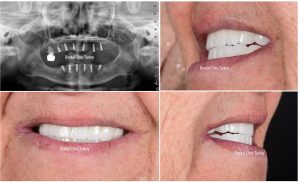

Bei Patienten mit gutem Allgemeinzustand und vollendetem Wachstumsalter kann das Implantat nach Beurteilung der Eignung der Knochenstruktur mittels Panoramaröntgen eingesetzt werden. Das Implantat kann angewendet werden, wenn Ihre Krankheit bei chronischen Krankheiten wie Diabetes, Blutdruck oder Herz unter Kontrolle ist.